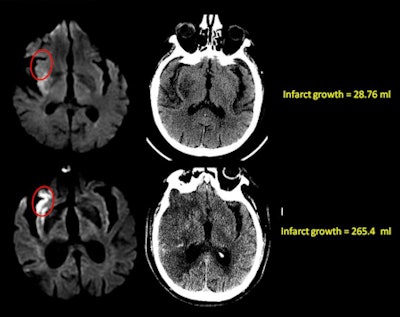

Dr. Seyedmehdi Payabvash, Lev, and colleagues showed that patients with very similar strokes except for the presence of insular involvement were demonstrating very different outcomes. Patients with insular involvement had significantly greater infarct growth into the penumbra in the subsequent 24 hours.

"It turned out the 25% [insular involvement] threshold was the threshold for infarct tissue growth versus no tissue growth," he said, adding that the results were both well-dichotomized and definitive. Patients who had zero to 25% insular infarct at admission had very little infarct growth, while patients with 25% to 100% insular involvement ended up with very large infarcts in the subsequent two days.

Patients with more than 50% involvement at admission had a median infarct growth of about 50 mL when recanalization was successful, compared with 200 mL when it was unsuccessful, he said. On the other hand, patients with less than 50% involvement at admission -- whether or not recanalization was successful -- had low infarct growth with a median of 50 mL.